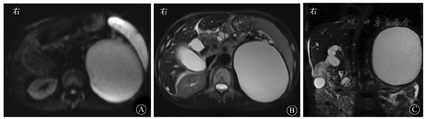

血常规WBC计数为2.74×109/L,RBC计数为3.12×1012/L,PLT计数为84×109/L。血清淀粉酶为112 U/L,胆红素水平正常。肿瘤标志物:AFP正常,CEA为11.07 μg/L,CA19-9为205.50 kU/L,CA125为116.90 kU/L。HBsAg为172.62 mIU/mL,其他乙型肝炎标志物均正常。2016年6月24日,上腹部CT平扫和增强(图1)示:①胆系扩张,胆总管下段有软组织密度影并强化,需考虑占位可能;②胆总管下段多发结石;③慢性胰腺炎并胰管明显扩张;④胆囊结石并胆囊炎;⑤肝硬化;⑥左肾结石,左肾巨大囊肿。MRI和MRCP检查(图2)示:①胆总管下段结石并胆系扩张;②胆总管下段狭窄,需排除占位;③左肾区巨大囊肿。7月2日行内镜下逆行胰胆管造影术(endoscopic retrograde cholangiopancreatography,ERCP),内镜显示食管静脉曲张(重度),胆管造影示胆总管中段明显狭窄,狭窄处长约2.0 cm,狭窄以上肝外胆管扩张,术中胆管腔内超声(intraductal ultrasonography,IDUS)检查狭窄处胆管未见明显异常,造影未见明确结石影,沿胆总管导丝置入覆膜金属支架于狭窄处。7月7日泌尿系统多普勒超声检查示左肾窝异常回声团块,考虑左肾囊肿可能。7月9日计算机断层扫描泌尿系统延时成像(computed tomographic urography,CTU)(图3)示:左肾区囊性病灶未见造影剂进入,提示假性囊肿形成可能性大。7月20日肝脏静脉血管造影(computed tomographic venography,CTV)(图4)示:肠系膜上静脉血栓形成,门静脉主干起始处闭塞,门静脉海绵样变性。8月1日复查CT增强(图5)示:①肝内胆管扩张、胆总管内置管术后改变。②慢性胰腺炎;胰尾囊肿引流术后,囊腔内积气。

影像科余晨主治医师:成人胆总管狭窄可继发于各种良恶性病变,拥有广泛的病因疾病谱。良性狭窄的病因包括医源性胰腺炎、急性或慢性胰腺炎、胆总管结石、原发性硬化性胆管炎、IgG4相关硬化性胆管炎、肝移植、复发性化脓性胆管炎、Mirizzi综合征、获得性免疫缺陷综合征相关胆管疾病和Oddi括约肌功能障碍等。恶性狭窄的病因包括胆管上皮癌、胰腺癌和壶腹周围癌。少见的病因包括胆道炎性假瘤、胆囊癌、肝癌、胆道转移癌、肝门部或胰周淋巴结肿大压迫继发胆系扩张[1]。影像学检查尤其是MRI平扫和增强与MRCP,是鉴别胆系梗阻病因较为理想的无创性方法。既往研究表明,恶性病变引起的胆道梗阻相较于良性病变更易出现以下倾向:首先,恶性病变所致的胆管壁增厚程度较良性病变更明显,病变累及范围更广,其上游胆管扩张也更为明显;其次,胆管恶性病变强化较良性病变更为明显,持续时间也更久[2];再次,胆管恶性病变在弥散加权成像(diffusion weighted imaging,DWI)上表现为更高的信号,提示其弥散受限程度更高[3];最后,胆管恶性病变更多表现为胆道偏心性狭窄,并且增厚管壁的内外缘更加毛糙、不光整[1]。综合患者在南昌大学第一附属医院的MRI和MRCP检查,首先,胆管狭窄位于胆总管下段,局部胆管壁增厚程度虽较明显,但累及长度较短,其上游胆管虽明显扩张,但其扩张程度与狭窄上方的结石直径相仿,故考虑其扩张原因应更多地归咎于狭窄上方的结石;其次,胆总管下段狭窄处管壁呈环形对称性增厚且管壁外缘较光整、轻中度强化;最后,DWI图像上的病灶信号不高,且肝门区未见明显恶性肿大淋巴结。以上这些影像学表现并不符合恶性病变的影像特征,故考虑胆总管下段梗阻为良性炎性病变所致,以慢性胰腺炎所引起的胆总管下段炎性狭窄的可能性最大。另外,患者胰胆管同时明显扩张,需要与胰头癌或壶腹周围癌所致的"双管征"进行鉴别诊断,患者胰管明显扩张的同时可见胰管钙化灶和胰腺结石影,提示胰管扩张为慢性胰腺炎所致,而并非由胰胆管共同开口处的病变所致。CA19-9升高虽常见于胰胆管和胃、肠道来源的恶性肿瘤,但低浓度增高和一过性增高亦可见于慢性胰腺炎、胆石症、肝硬化、肾功能不全、糖尿病等,故建议在治疗期间随诊复查该项指标。

影像科何来昌副主任医师:CT和MRI检查均提示左侧中上腹部巨大囊肿性肿块,胰体尾部、脾脏和脾血管均向前移位,提示囊性病变位于左侧腹膜后间隙内,而腹膜后间隙内实质性器官包括胰腺、肾脏和肾上腺,需要对这些脏器来源的囊性病变进行逐一排除。结合患者的临床表现,影像学检查有慢性胰腺炎的特征性表现,确实需考虑胰腺假性囊肿的可能。然而影像学图像上可见左侧肾上腺完整并轻度上移,左肾中上部肾实质萎缩,左肾整体轻度下移,囊肿与左肾实质分界不清,而与胰腺分界较为清晰,故还要考虑囊性病变为左肾来源的可能性。左肾来源的囊性病变主要包括肾囊肿,囊性肾癌,肾盂、肾盏囊性扩张积水。其中,肾囊肿包括单纯性肾囊肿和复杂性肾囊肿。单纯性肾囊肿的影像学表现为肾实质内边缘光整、锐利,囊壁菲薄且无强化的囊性占位,囊液呈水样密度或信号影,增强亦无强化。复杂性肾囊肿是单纯肾囊肿合并出血或感染等炎性反应刺激,可使局部机化、钙化、血管及肉芽肿形成,其囊壁通常增厚,囊液成分复杂,其影像学表现也较为多变,可于囊内或囊壁出现钙化,囊内液体可因含有蛋白质、黏液成分而呈现较高的密度和磁共振序列上的复杂信号,囊内多无分隔和壁结节影,其囊壁可有强化,而囊内液体则无明显强化。囊性肾癌则多可见强化的囊壁、囊内分隔和壁结节影[7]。肾盂、肾盏囊性扩张积水多为肾结石或炎性反应继发,影像学检查可发现原发病变,CTU检查多可见造影剂进入囊性扩张的肾盂、肾盏内。本例患者CT和MRI检查均提示囊性病灶囊壁较厚、囊壁钙化,囊内未发现明确的分隔和壁结节,囊液密度较高且弥散受限,增强扫描囊壁轻度强化,然而CTU检查未见造影剂进入囊性病灶内,故考虑复杂性肾囊肿的可能性大。目前,从影像学检查上尚难确诊是胰腺假性囊肿还是左肾囊肿,建议穿刺检测分析囊内成分,可进一步将其与胰腺假性囊肿进行鉴别。